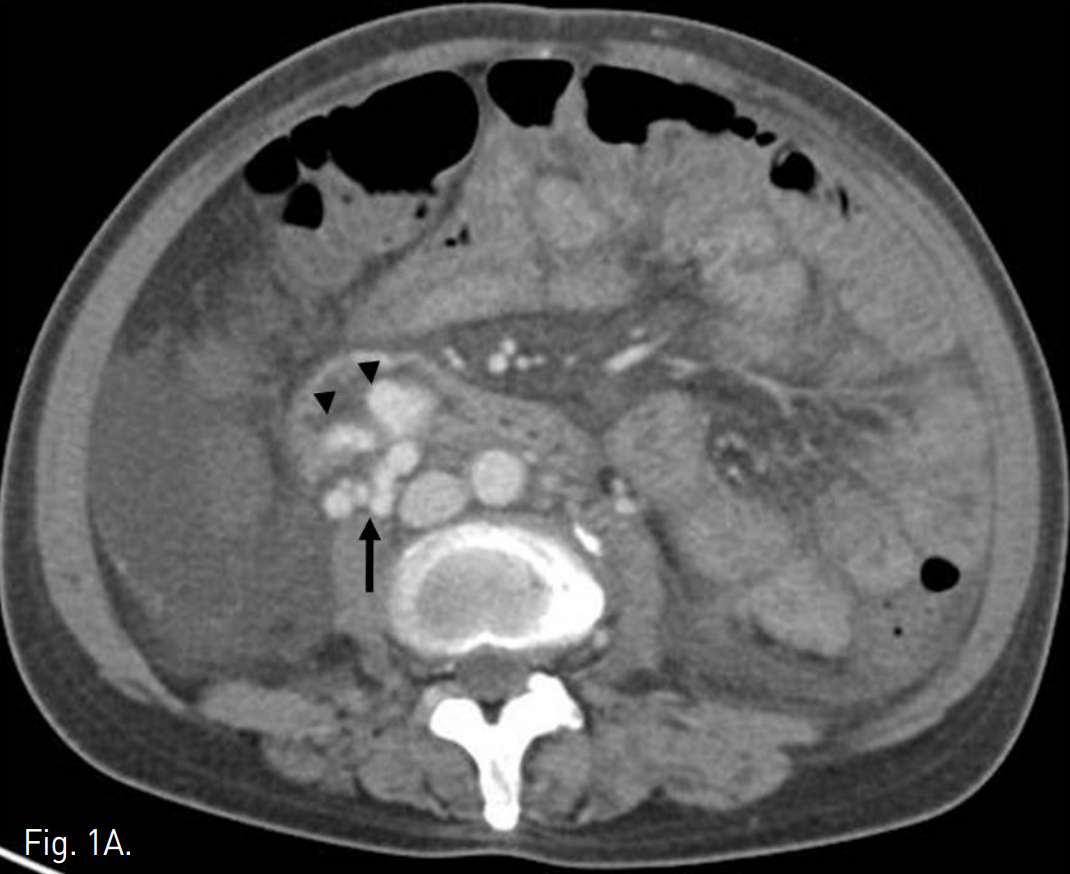

복부 CT에서 정맥류로 생각되는 확장되고 구불구불한 모양의 이상 혈관구조가 주문맥 윈위부에서 기시하여 우하복부 장간막을 따라 있으며, 일부 혈관구조가 소장 벽에 노출되어 있는 모습을 보인다. 그 외에 위, 식도에도 정맥류가 관찰되고 복수와 간 표면의 불규칙화, 경한 비장종대, 소장의 점막하부종이 동반되어 있다(Fig. 1A, B).

Fig. 1

A. Contrast-enhanced abdominal CT shows a tortuous and dilated vasculature (arrow) suggesting varix is located in mesentery of right lower quadrant area and some branching vessels from varix are protruding into adjacent intestinal wall (arrowheads).

B. Coronal scans show entire course of the varix supplied from main portal vein.